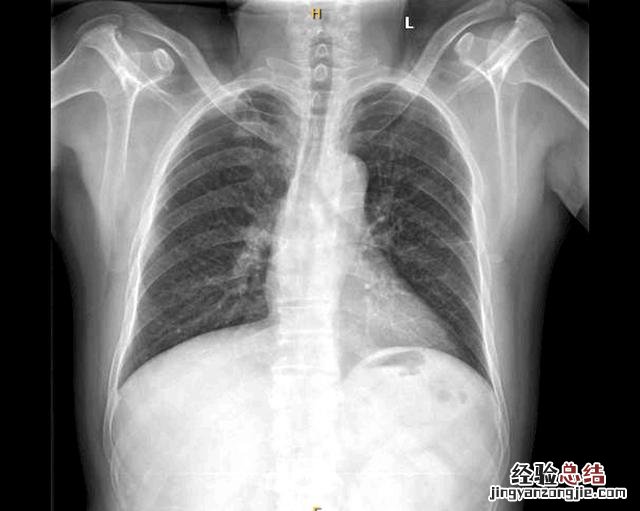

文章插图

(患者胸片结果)